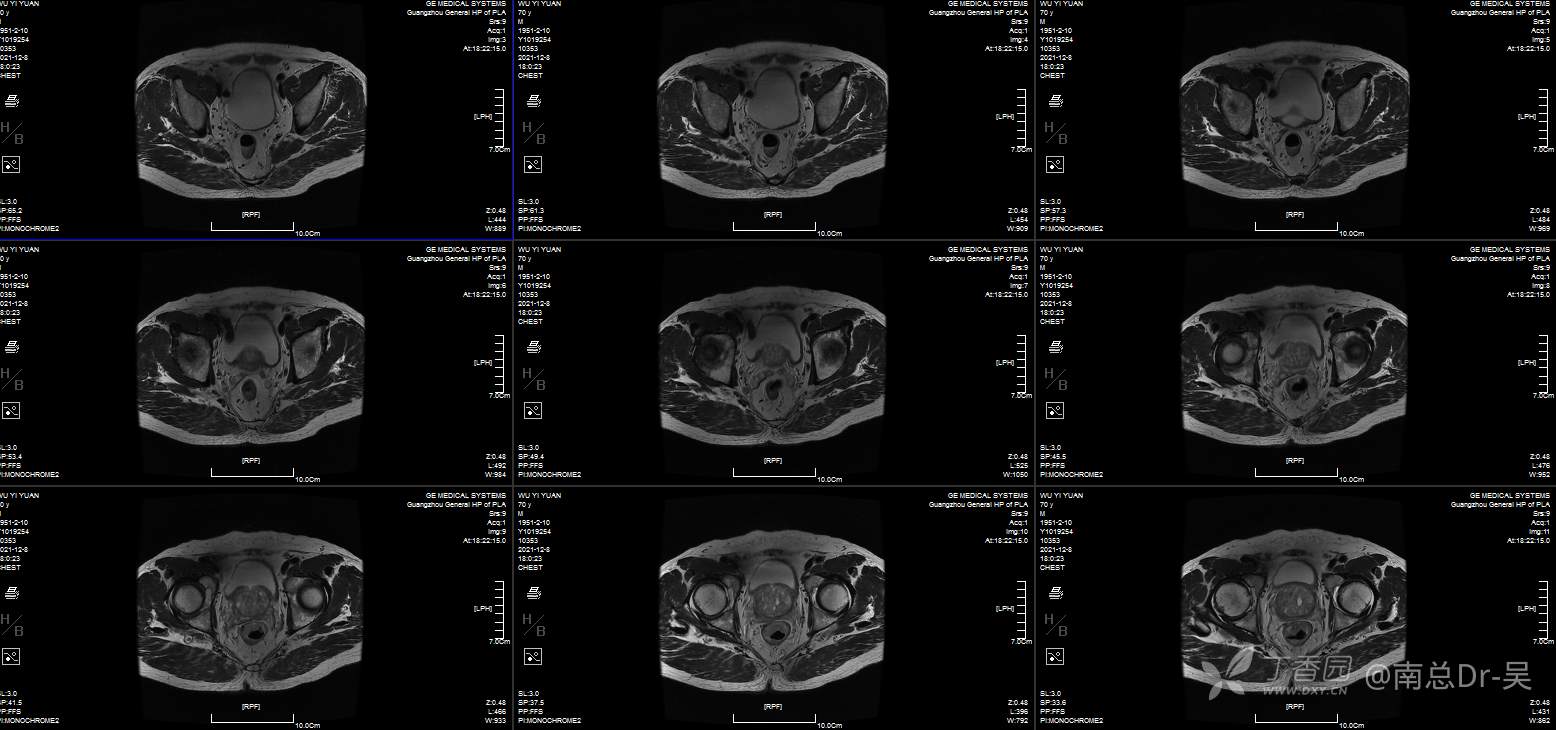

男性患者,81岁,诊断为:超低位直肠癌。肠镜提示距肛门2cm直肠占位,病理:中分化腺癌。患者本人有着强烈的保肛愿望,且评估该患者术前肛门功能良好,因此如何实施高质量的保肛手术是值得关注的问题。

低位直肠癌保肛手术方式多种多样,有ISR、TATME、Bacon、PAKS等等,但每一种手术有着其自身的优劣势,因此合适的手术是保证患者最大获益的前提。

直肠癌经肛拖出适形切除肛门功能重建术是一种两期法的手术,一期先经腹腔镜下直肠癌经肛外翻拖出切除,直视下适形切除肿瘤,尽量保留健侧的肛门括约肌。同时将近端结肠拖出至肛门外约4-6cm,待肠管与肛管自然愈合后约3周,局麻下行肠管切除、肛门整形术。

该手术其实是ISR+NOSES+BACON式的结合及改良,优势为“”“四无一有”腹部无切口、无引流管、无吻合口、无造口、有肛门功能。术后第1天即可恢复进食,符合ERAS理念,后续的辅助治疗可提前,术后5天可出院。

手术的技术要点在于腹腔镜下腹腔组的分离要达到括约肌间平面,肛门组经肛将直肠及肿瘤一起外翻拖出肛外,经肛门直视下适形切除病灶,遵循远切缘大于1cm的原则下,肿瘤侧多切,健侧多保留原则,目的是为多保留肛门括约肌,避免了以往的直线切除的健侧括约肌过多切除,影响术后肛门功能。残存的肛门外括约肌及耻骨直肠肌进行重建修复,重建新的肛直肠角,进一步改善术后肛门功能。近端结肠拖出长度以系膜松弛为原则,目的是为了预防术后早期出现的拖出肠管坏死,这方面技巧日后再说。最后二期的整形切除手术更需技巧,一是多保留粘膜,二是尽量切除增生的纤维瘢痕组织,三是缝合时带部分括约肌,达到缝合结束后粘膜是内翻,肛门外观良好。同时避免术后出现肛门狭窄、粘膜脱垂及少见的直肠漏。